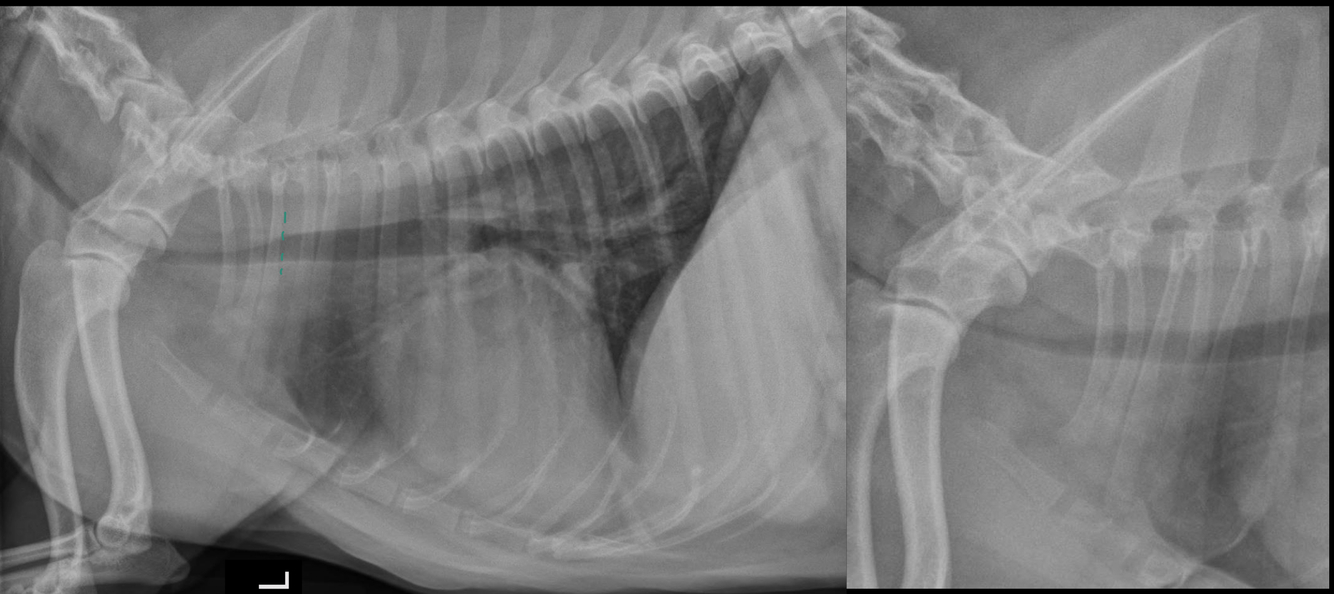

Tracheal collapse:

A

redundant trachealis membrane